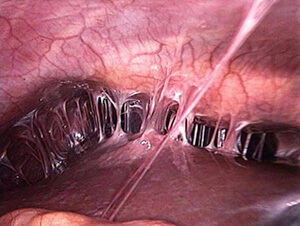

Sepleşme keseli – käbir keselleriň täsiri netijesinde garyn boşlugynda özara sepleşmeleriň döremegi bilen ýüze çykýan ýagdaýy häsiýetlendirmek üçin ulanylýan düşünjedir. Bu ýagdaýyň döremegine içki agzalaryň şikeslenmegi, şol sanda hirurgiki şikeslenmeler hem sebäp bolup biler. Köplenç ýagdaýlarda sepleşme keseliniň döremegine hirurg lukmanyň öz işinde göýberýän kemçiligi höküminde garaman, hirurgiki usul bilen bejerginiň umumy kemçiligi höküminde garalmagy dogry bolardy.

Garyn boşlugynyň hirurgiýasynyň kämilleşmegi bilen, köp hirurg lukmanlary garyn boşlugynda gaýtadan geçirilýän operasiýanyň gidişinde, içki agzalaryň biri-birine ýelmeşendigini we operasiýanyň gidişini kynlaşdyrýandygyny syn edipdirler. Sepleşme keseliniň bejerilşi we onyň öňüni almagyň usullary lukman Paýryň başlangyjy bilen XX asyryň başlaryndan bäri öwrenilmegini dowam etsede, bu kesel babatda ýüze çykýan soraglar bu günki günümizde hem öz ähmiýetini ýitirmän gelýär.